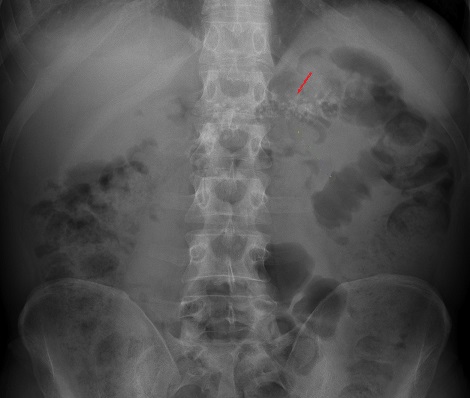

Image radiologique ASP de

face des calcifications parenchymateuse d'une

pancreatite chronique . Image de calcification en ce

cas situe a la region gauche du L1 , L2 est en vue

et moins nette que le cliche ASP de face au dessus

par en consommation avec image de ileus gazeuse du

colon transverse |